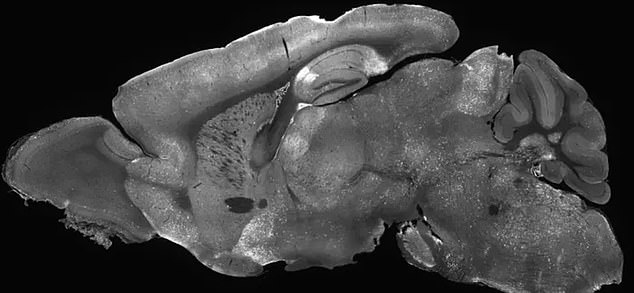

The above is the cross section of the brain of a mouse in the study. The highlighted areas represent locations where the adenovirus delivered the treatment to the brain